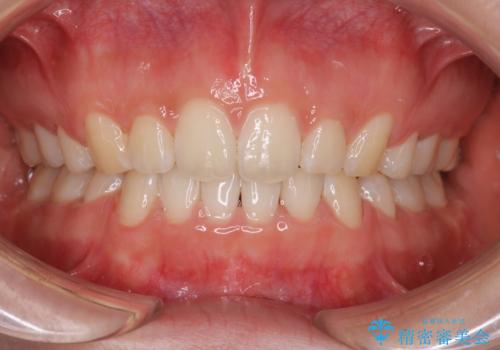

前歯をしっかり下げることで、口元がすっきりしました。